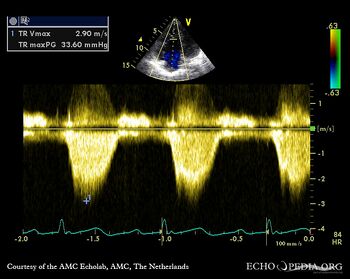

Ebstein anomaly

A4CH: Color Doppler, severe tricuspid regurgitation Continuous-wave signal of severe tricuspid regurgitation, pulmonary hypertension